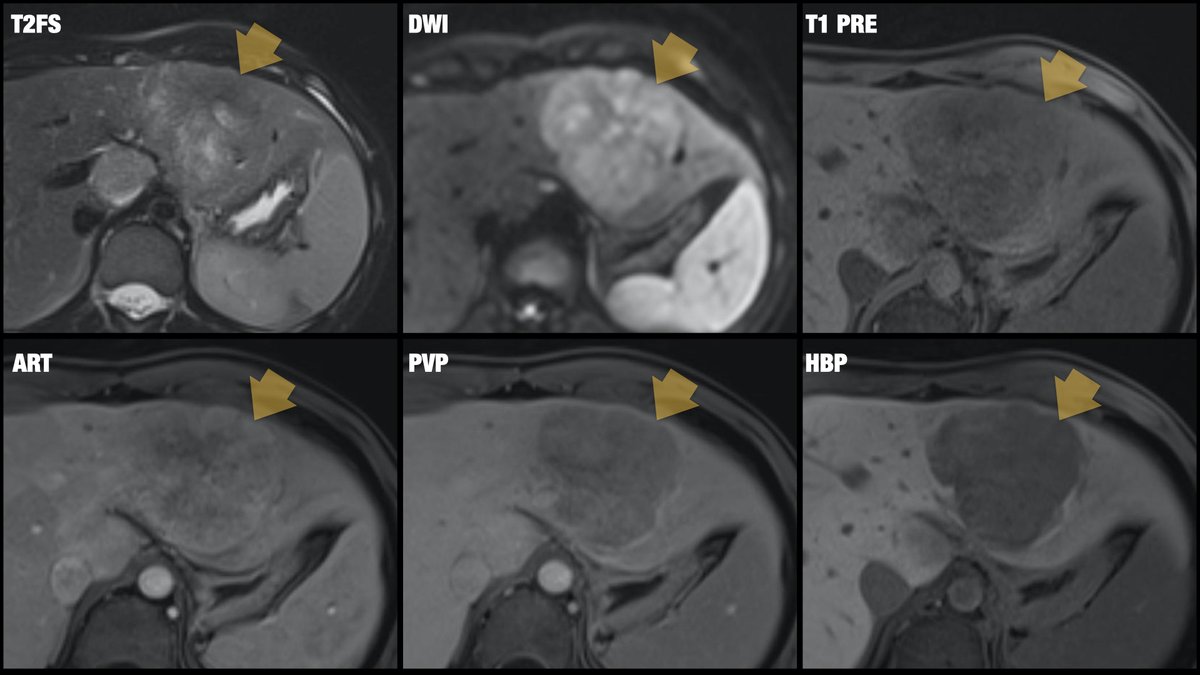

[2/2] Eovist/Primovist-enhanced liver MRI performed: heterogeneous mass, restricted diffusion, central scar with septa, no contrast uptake on hepatobiliary phase. Rare but classic! Diagnosis? Brigham and Women's Radiology @AURtweet FOAMrad SAR Resident and Fellow Section Future Radiology Residents Harvard Macy CBR #MedEd

[2/2] Eovist/Primovist-enhanced liver MRI performed: heterogeneous mass, restricted diffusion, central scar with septa, no contrast uptake on hepatobiliary phase. Rare but classic! Diagnosis? <a href="/BrighamRad/">Brigham and Women's Radiology</a> @AURtweet <a href="/FOAMrad/">FOAMrad</a> <a href="/SAR_RFS/">SAR Resident and Fellow Section</a> <a href="/futureradres/">Future Radiology Residents</a> <a href="/HarvardMacy/">Harvard Macy</a> <a href="/CBRadiologia/">CBR</a> #MedEd